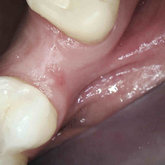

We make it a priority to incorporate the latest in dental technology in everything we do at our practice. ...